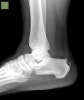

Lateral view X-ray에서 아킬레스 힘줄의 석회화, 뼈돌기, 발꿈치 뼈의 후상방 부위 돌출 등을 볼 수 있습니다.

X-ray : 허글런드 변형(Haglund deformity)